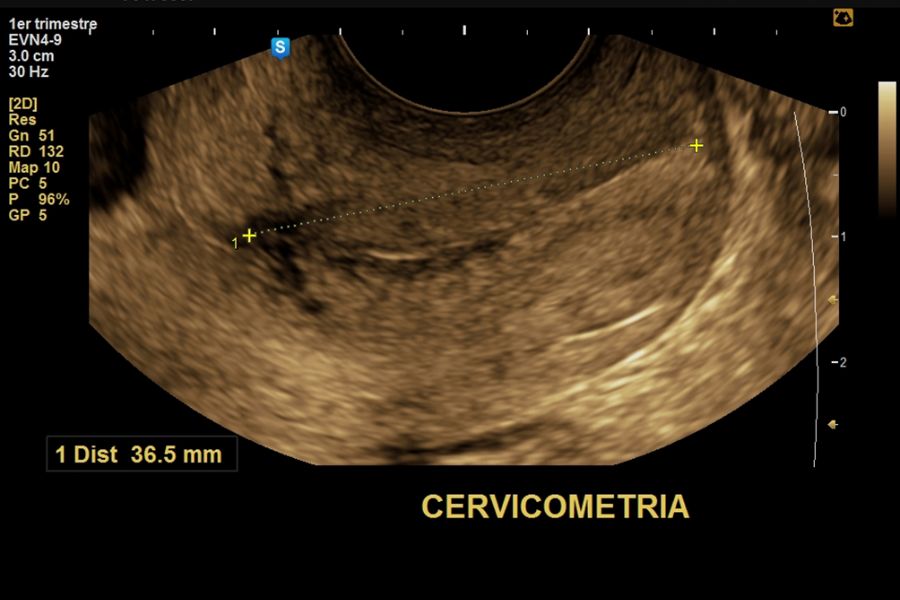

Cervicometría: PARA PREDICCIÓN DE PARTO PREMATURO

Cervicometría